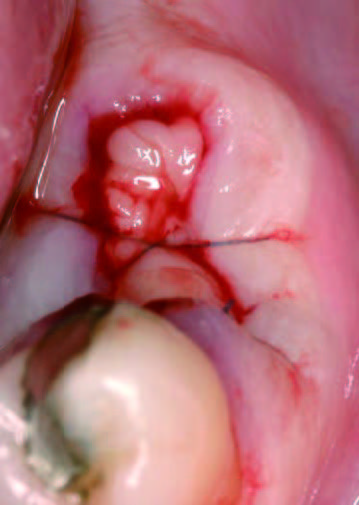

15日後歯肉の状態

15日後歯肉の状態

抜歯後にできた穴にPRGFを注入すると、上皮や骨の再生が促進され、短期間で穴が塞がります。また、抜歯後の痛みや腫れも軽減されるため、回復がスムーズに進みます。

一方、自然治癒の場合、穴が完全に塞がるまでに数ヶ月かかることがあります。その間に、ドライソケット(抜歯窩治癒不全)を引き起こしたり、食べ物が詰まることで痛みや悪臭が発生することもあります。